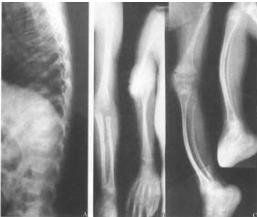

(3)病灶呈瀰漫性多發的密度增大的圓形、橢圓形、圓圈狀、結節狀陰影,其形態走行,部分與骨的長軸一致。

(4)病灶多累及長骨的兩端,密集於乾骺端及骨骺,以及骨盆、手、足及不規則骨。越靠近關節病灶越密集,且密度越濃。病灶可相互融合成片而遮蓋正常骨組織。

(5)密度增濃的斑點狀病灶的邊緣不甚清晰銳利,越靠近中心部位密度越濃,邊緣部位密度略淡。

(6)病灶侵及骨的松質骨。骨膜及關節軟骨不受侵犯,故關節間隙光整清晰。

脆弱性骨硬化1、X 線檢查是發現和診斷本病的主要依據。X 線上病灶呈瀰漫多發的圓形、類圓形或融合成條狀及團塊狀緻密影,位於骨松質內,走行與骨長軸一致,雙側基本對稱,大小在數毫米至2 cm 之間;越靠近關節病灶越密集密度也越高;絕大多數病灶中心密度高邊緣密度低,也有少數病灶中心密度偏低,但其邊緣均較清楚;病灶不侵犯骨膜及關節軟骨,關節間隙清晰。